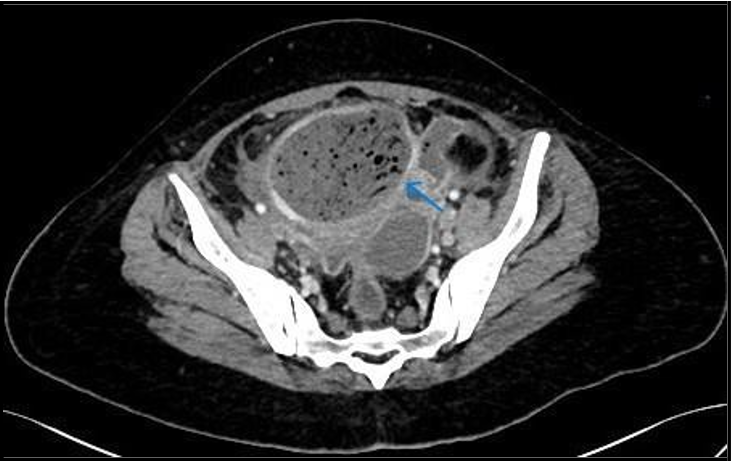

A CT scan of the abdomen and pelvis with contrast was performed to determine the cause of sepsis. It revealed a large, thick, enhancing walled-off area in the pelvis adjacent to the fundus of the uterus, containing multiple internal air locules with indistinct walls at places, and continuing air tracks. (Figure 1, 2). This represented an infected embolectomy-treated  subserosal  fibroid.  There  were  multiple intercommunicating pelvic infection collections in the cul-de-sac and vesico-uterine pouch (Figure 3). Diffuse peritonitis, omentomesenteric congestion, and edematous bowel loops were observed. Multiple prominent pelvic sidewall nodes were also noted. Therefore, rupture of pyomyoma with intraperitoneal spillage of infected content resulting in peritonitis is suggested.

Figure 1: Axial images of contrast enhanced CT scan showing air containing mid pelvic structure/pyomyoma (arrow).